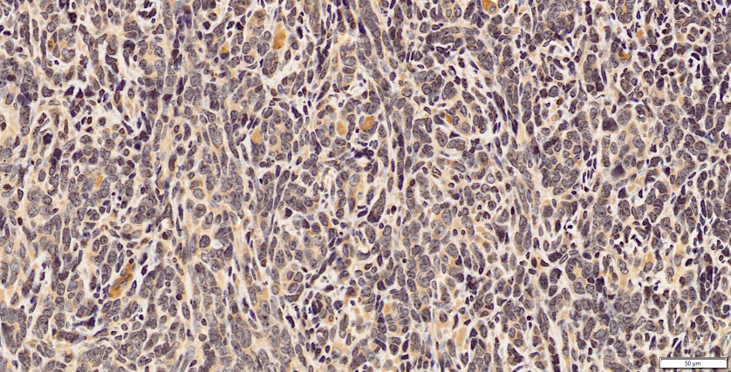

CXCR4 in Mouse Spleen. CXCR4 was detected in immersion fixed frozen sections of mouse spleen using Rat Anti-Mouse CXCR4 Monoclonal Antibody (Catalog # MAB21651) at 15 µg/mL overnight at 4 °C. Tissue was stained using the Anti-Rat HRP-DAB Cell & Tissue Staining Kit (brown; Catalog # CTS017) and counterstained with hematoxylin (blue). Lower panel shows a lack of labeling if primary antibodies are omitted and tissue is stained only with secondary antibody followed by incubation with detection reagents. View our protocol for Chromogenic IHC Staining of Frozen Tissue Sections.